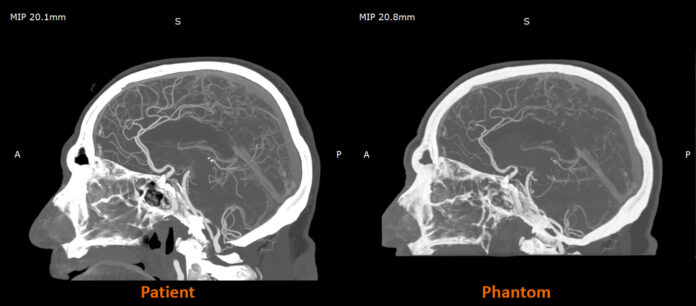

RadioMatrix is the first 3D printing material engineered to offer precise control over radiopacity, enabling production of patient-specific anatomical models with predictable visibility on CT and other X-ray imaging systems. Stratasys developed the material to support more advanced medical imaging workflows, and its performance has been validated in studies conducted with Siemens Healthineers. According to the company, the collaboration demonstrated that RadioMatrix phantoms can replicate human tissue with deviations as low as single Hounsfield units in key structures such as grey matter and vasculature.

Stratasys said the material is already showing impact in early deployments. In the United Kingdom, projects with CPI and Beaumont Hospital have used radio-realistic cerebral angiography phantoms to improve training environments and enhance control and repeatability in imaging research. By pairing Digital Anatomy 3D printing technology with the new radiopaque material, Stratasys and Siemens Healthineers are developing anatomically detailed, radio-accurate models that can serve as scalable and ethical alternatives to cadavers for imaging education, protocol development and algorithm testing.